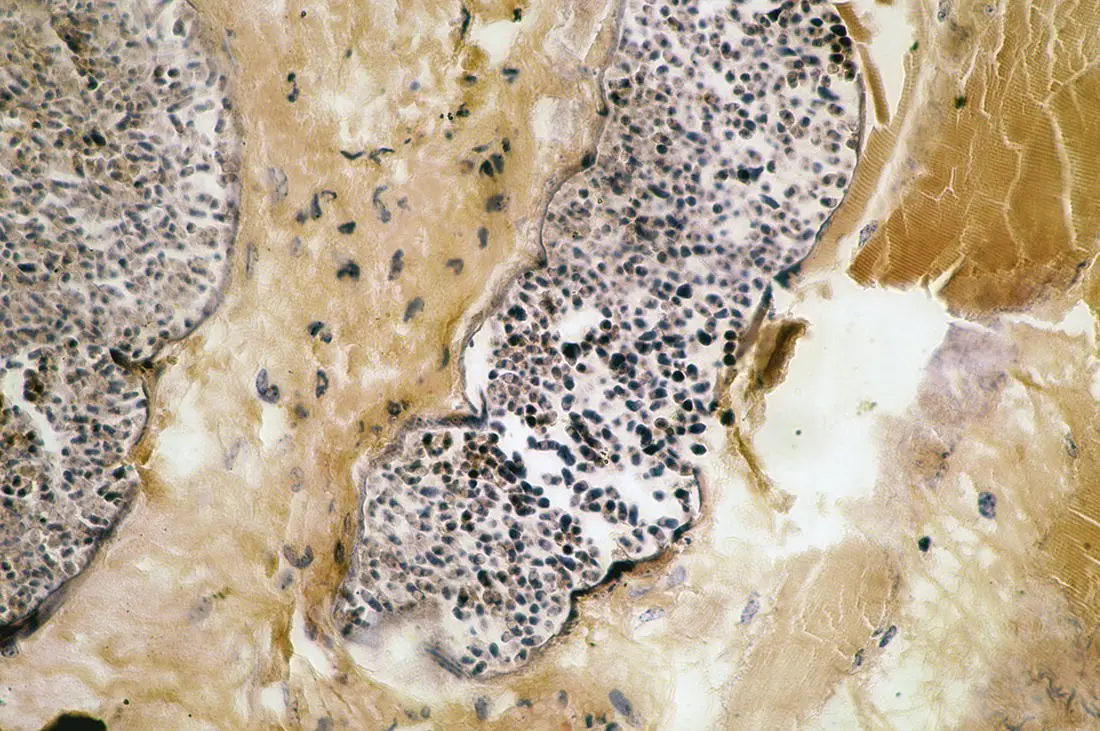

Figure 3.15 Transverse section through a sarcocysts of Sarcocystis muris in the trachea of a mouse.